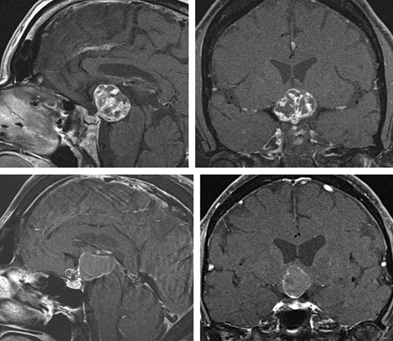

The well-recognized topography of a craniopharyngioma is of either seller or para-seller partially solid mass, cystic, or calcified mass (Figure 2).

A CT scan can show calcification better than other imaging, while MRI can appreciably delineate the extent of the tumor and its relation to the hypothalamus and adjacent structures, therefore, it is sound imaging preoperatively; moreover, MRA can differentiate the tumor mass from vascular malformations like aneurysm (Figure 2).15,16

MRI of the pituitary 05.02 (Figure 4).

The imaging findings are those of Craniopharyngioma (Figure 4).